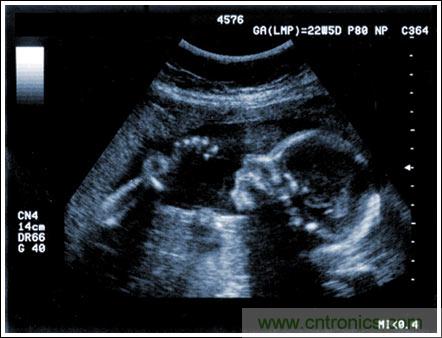

通過發(fā)射超聲能量進(jìn)入人體,接收并處理返回的反射信號,相控陣超聲系統(tǒng)可以生成體內(nèi)器官和結(jié)構(gòu)的圖像,映射血液流動和組織運(yùn)動,同時提供高準(zhǔn)確度的血流速度信息。傳統(tǒng)設(shè)計(jì)中,構(gòu)建這樣的成像系統(tǒng)需要大量的高性能相控陣發(fā)射器和接收器,使得車載設(shè)備體積龐大且價格昂貴。近年來,隨著集成工藝的進(jìn)步,設(shè)計(jì)人員能夠獲得小尺寸、低成本而且高度便攜的成像系統(tǒng)方案,并可達(dá)到接近大型成像設(shè)備的性能指標(biāo)。而新的設(shè)計(jì)挑戰(zhàn)依然存在,即在進(jìn)一步提高方案集成度的同時提高系統(tǒng)性能和診斷能力。